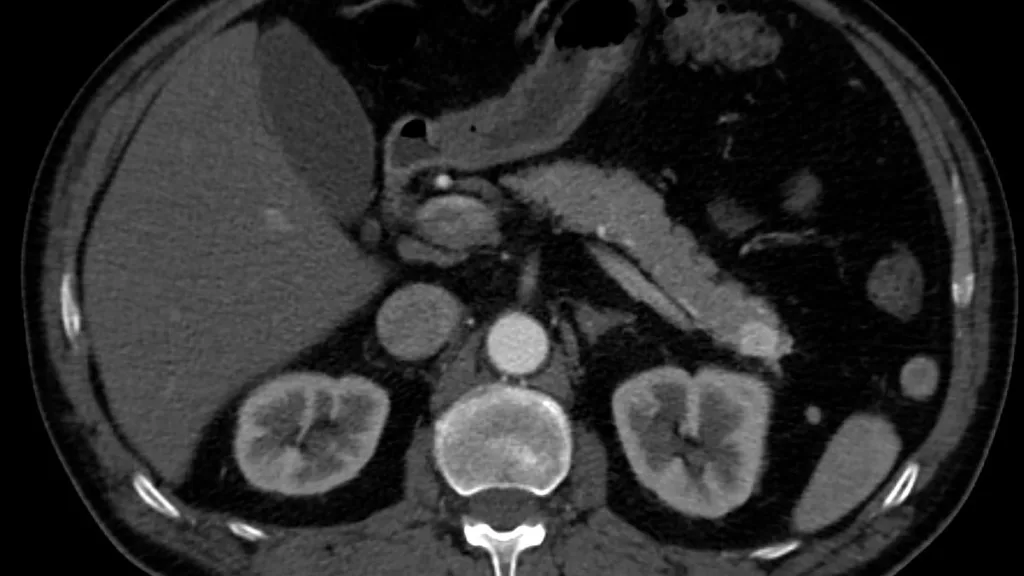

Cáncer de páncreas

Globalmente, noviembre es el mes de concientización para este cáncer, cuya tasa de supervivencia es una de las más bajas. Más del 80% de los casos se diagnostican en etapas avanzadas.

La participación de Oncomeds en protocolos internacionales acerca a pacientes chilenos a terapias moleculares e inmunoterapias experimentales, la única vía para revertir su curso.